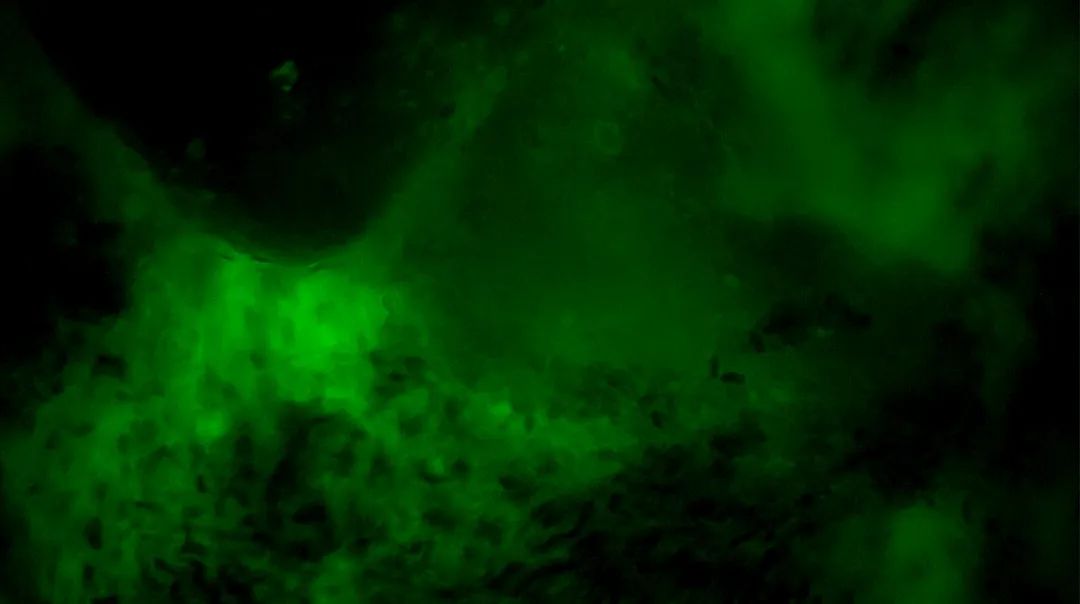

▲医生在术中使用EndoSCell™扫查瘤腔

本次手术,医生在术中导航及术中超声指导下将肿瘤病灶主体切除后,使用EndoSCell™扫查离体肿瘤以观察阳性细胞形态作为对照。随后使用EndoSCell™在体扫查全瘤腔,在偏后侧缘处发现了一处细胞核呈明显异型、分布密集且不规则的组织,判断为残留病灶并进行扩切。接着,再次使用EndoSCell™检查扩切处是否切干净,发现仍有残留并进行扩切。通过这种逐层扫查、切除的方式,最终在第3次扫查时,图像显示整个瘤腔均为正常细胞形态,由此判定切缘已达全部阴性,可进入关颅等后续步骤。

3次切缘扫查的EndoSCell™细胞图像

1

阳性,细胞核异型、密集、分布不均匀

2

3

阴性,细胞核形态正常、分布均匀